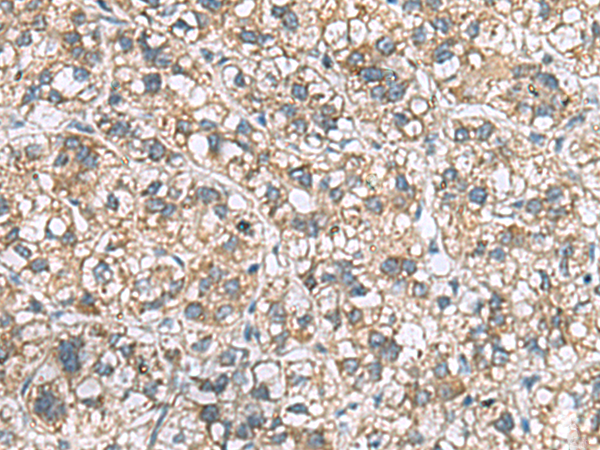

分类: 科研抗体货号: P03325别名: PKDR1; SAMD6; NPHP16; ANKRD14应用: IHC反应种属: Human, Mouse, Rat